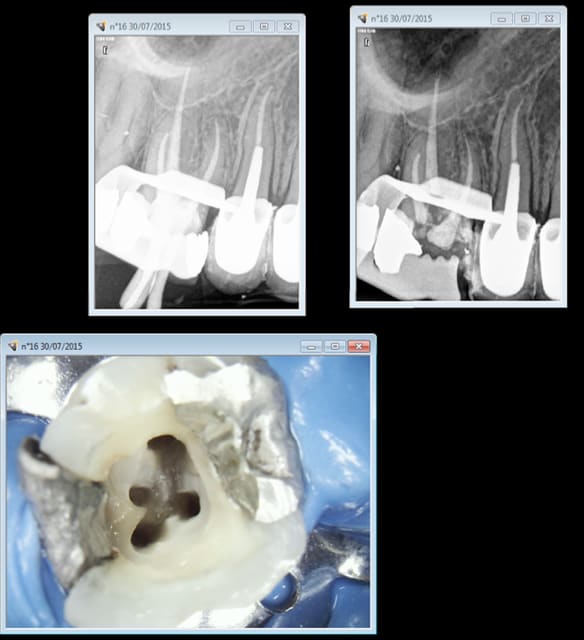

Endo 16 + sc 33. Costeaude la racine DV.

Capture d e cran 2015 07 30 15.33 - Eugenol

Ca m'arrive de foirer mais rarement, ici racine distale de 16 manque 2 mm. je n'essaie pas de forcer outre mesure et d'arriver à tout prix à l'apex.

Capture d e cran 2015 07 30 16.30 - Eugenol

T'es fâché avec les racines DV des 1ères molaires sup ?